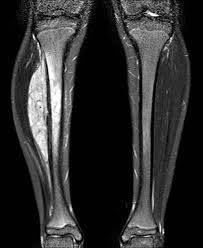

| Causa: A causa é desconhecida. Não parece ser hereditária. São tumores extremamente raros em negros e asiáticos. Patologia: Os tumores de Ewing correspondem a tumores de células pequenas, redondas e azuis. Devem ser diferenciados de outros tumores que apresentam as mesmas características morfológicas, como neuroblastoma, rabdomiossarcoma e linfoma. Para tal são necessários estudos de imunohistoquímica, citogenética e biologia molecular. Apresentação Clínica Dor ou edema no sítio primário do tumor são os sinais de apresentação mais comuns. Em cerca de 25% dos pacientes ocorrem também sintomas sistêmicos como febre e perda de peso. Estes sintomas podem, frequentemente, levar à confusão diagnóstica com osteomielite. Os sintomas podem durar meses antes que o paciente procure atenção médica em até 50% dos casos. Cerca de 25% dos pacientes se apresentam com metástases ao diagnóstico, que podem ocorrer em pulmão, osso e medula óssea. Aspecto Radiológico Pela radiografia simples podem-se observar lesões líticas ou mistas- lítica e esclerótica, com o aspecto característico de "casca de cebola". Sarcoma de Ewing-PPNET de tecido mole ocorre frequentemente próximo a ossos e pode ser difícil diferenciar de tumores ósseos primários. Em tumores da parede torácica, as costelas podem ser o sítio primário ou podem ser secundariamente envolvidas com grandes massas. Tratamento O tratamento de Sarcoma de Ewing e PPNET requer erradicação do tumor no local primário, com cirurgia e radioterapia; em sítios metastáticos ou micrometastáticos, com quimioterapia. Quase todos os doentes apresentam doença micrometastática (que não pode ser detectada pelos métodos habituais) ao diagnóstico. Logo, o tratamento de Sarcoma de Ewing e PPNET requer quimioterapia seguida de cirurgia ou radioterapia. Ainda não está estabelecida qual é a melhor forma de controle local: cirurgia ou radioterapia. Para obter-se um resultado ótimo é necessária a combinação racional das modalidades de tratamento. Fatores prognósticos adversos incluem presença de metástases ao diagnóstico, localização em ossos pélvicos, tumores grandes >100 ml ou >8 cm em diâmetro e idade superior a 17 anos. Fatores prognósticos positivos incluem boa resposta clínica e patológica (>90% necrose tumoral) à quimioterapia. Um "Intergroup Study Group" para Sarcoma de Ewing mostrou que a combinação de quimioterapia com VADRC alternada com IE foi superior, com Sobrevida Livre de Doenças (SLD) de 69% em 3 anos. Entretanto, pacientes com tumores metastáticos continuam a ter prognóstico mais reservado, com 20% de SLD em 4 anos. O acompanhamento a longo prazo evidenciou que 10 a 30% dos pacientes desenvolvem um segundo tumor em área irradiada. PPNET da Parede Torácica - Tumor de Askin Constitui-se em um tumor raro que surge em tecidos moles da parede torácica. É predominantemente observado em crianças e adultos jovens. O sintoma inicial mais comum é massa em parede torácica dolorosa ou indolor. Outros sintomas são dor no ombro, dispnéia, tosse, perda de peso e febre. Em 10% dos casos a doença é metastática ao diagnóstico. Imagens O Tumor de Askin geralmente é demonstrado como massas extra-pulmonares com ou sem destruição de costelas, frequentemente associadas com derrame pleural. Na tomografia computadorizada, observa-se uma massa em parede com extensão intratorácica, sendo que a lesão é geralmente heterogênea, devido à hemorragia e necrose. Tratamento O tratamento inclui quimioterapia, seguida de cirurgia para ressecção do tumor, ou radioterapia individualizada para cada caso. A taxa de sobrevida varia entre os estudos, mas são tumores localmente agressivos com prognóstico reservado, geralmente com resultado terapêutico pobre. Sarcoma de Ewing Tumor Neuroectodérmico Primitivo Periférico ![]() REFERÊNCIA BIBLIOGRÁFICA: http://www.inca.gov.br/conteudo_view.asp?id=345 POSTADO POR: RAFAEL DAMIÃO DA SILVA BRANCO GARCIA |